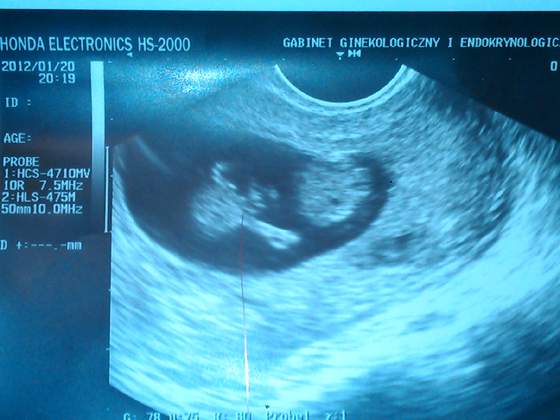

IMG083.jpg 11 tydzień